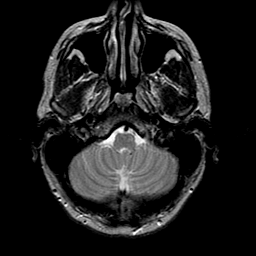

glioma overlay -- Slice #4

[Home][Help][Clinical] Slice 4